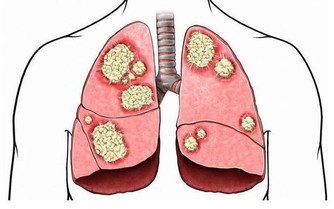

丑時肝經最旺,丑時(1:00—3:00)不眠,肝無法解除掉有毒之物,產生新鮮血液,因藏血不利,面呈青色,久之易患各類肝病。乙肝病毒攜帶者,是由於晚上經常不睡覺,人太虛弱了,也就是說秩序太亂了,病毒已經到了細胞裡了。

肝主疏泄,過子時不睡,可引起肝疏泄不利,肝氣鬱結,可見易怒,頭痛頭暈,眼紅,眼痛,耳鳴,耳聾,胸肋脹痛,女性月經不調,便秘,也可引起肝氣升發不足,人會目倦神疲,腰膝酸軟,暈眩,失眠,驚悸,精神恍惚,重則會暈倒在大街上,不省人事。

肝開竅於目,過子時不睡,易引起肝虛,則出現視力模糊、老花、夜盲、畏光、迎風流淚,等症狀,還會形成青光眼、白內障、眼底動脈硬化、視網膜病變等眼疾。

肝主筋,其華在爪,過子時不睡覺,會引起肝血不足,就出現筋痛,麻木,屈伸困難,痙攣抽搐,易造成灰指甲,缺鈣,髕骨軟化,癲癇病,骨質疏鬆等症。

肝與心,過子時不睡覺,可引起肝血不足,由於心主一身之血脈,肝有儲藏和調節血液的功能,會造成心臟供血不足,引起心慌、心顫等症狀,嚴重的形成心臟病、高血壓等心腦血管疾病。

3、睡眠的方法